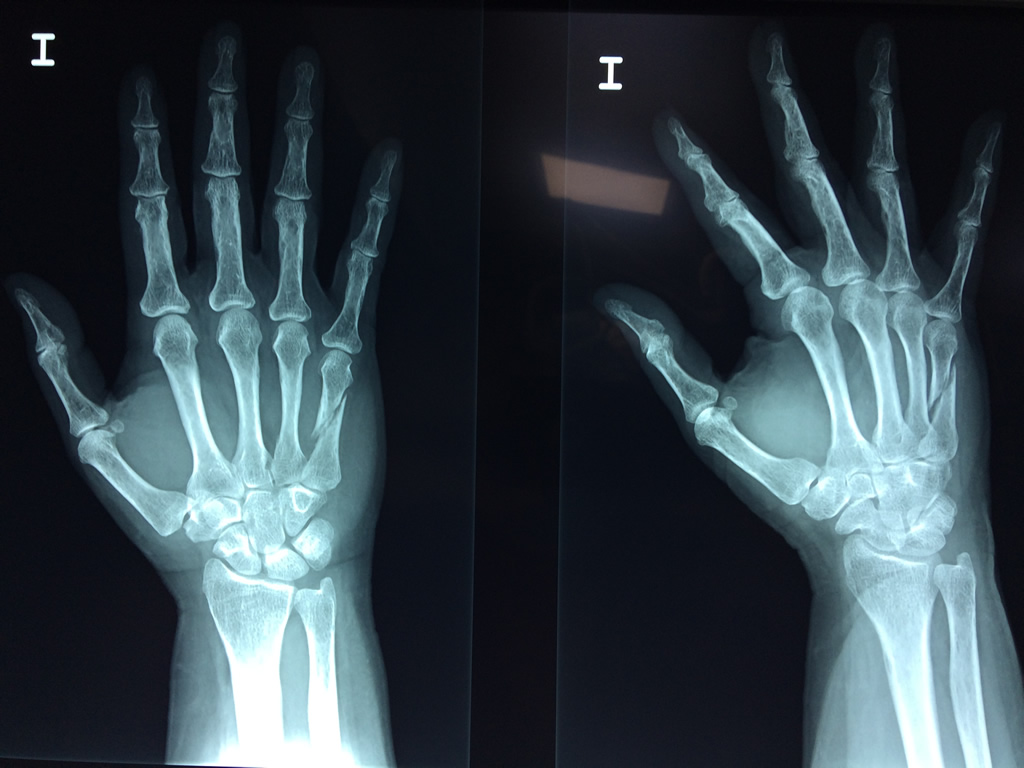

Cirugía de Muñeca y Mano

Los procedimientos más comunes en cirugía de la mano son aquellos destinados a reparar traumatismos, incluyendo lesiones de tendones, nervios, vasos sanguíneos, y articulaciones; huesos fracturados; y quemaduras, cortes, y otros daños de la piel.